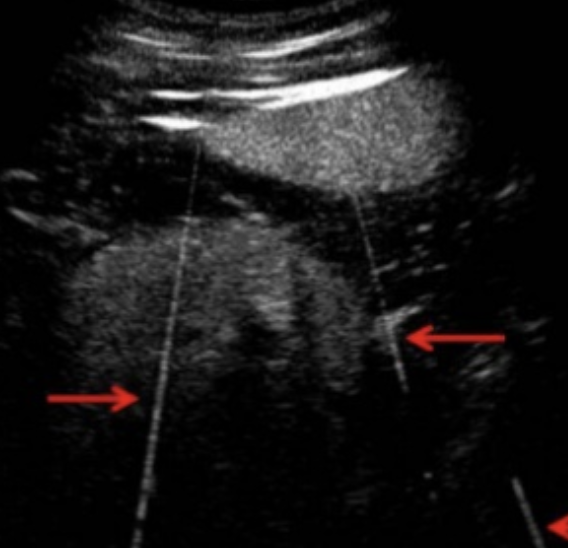

Name this artifact.

What is the cause of the artifact?

Electronic noise artifact: Stray electric signal from electric equipment such as lights, clippers, and electrocautery units may cause artifacts to appear that remain when the transducer is not in contact with the animal.